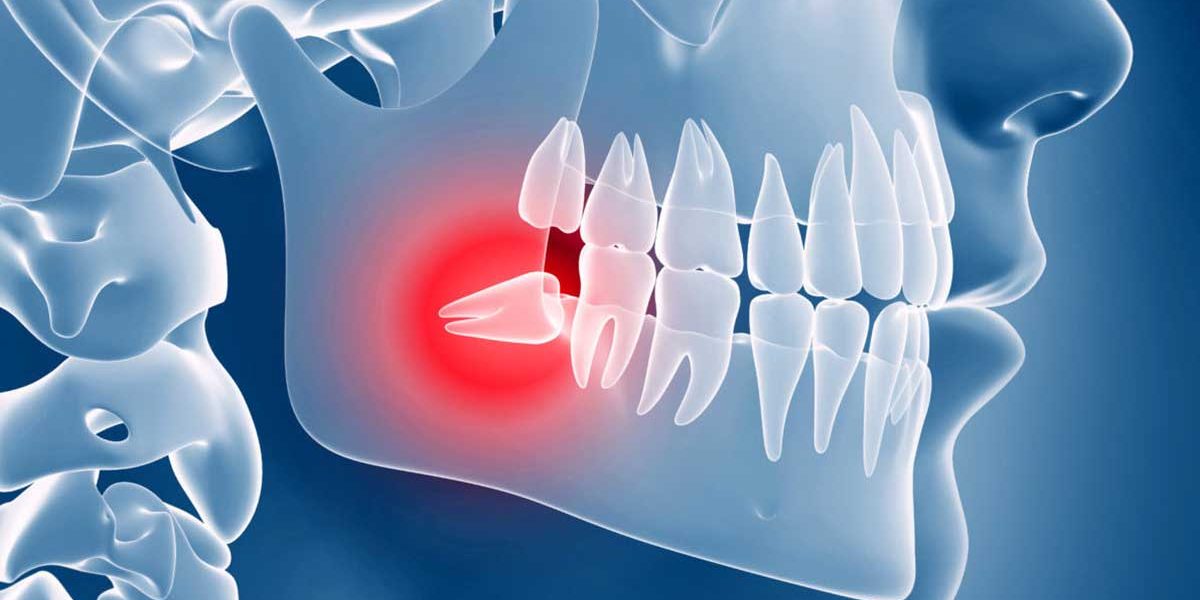

La nevralgia del trigemino è un grave dolore facciale dovuto a un malfunzionamento del 5° nervo cranico (nervo trigemino). Questo nervo trasporta le informazioni dal viso al cervello e controlla i muscoli implicati nella masticazione.. L'infiammazione del nervo trigemino, meglio conosciuta come nevralgia del trigemino, è una sindrome dolorosa e cronica che colpisce una coppia di nervi presenti in modo simmetrico a sinistra e a destra della testa. È più frequente che l'infiammazione colpisca il lato destro e interessi soggetti di sesso femminile che hanno superato i 50 anni.